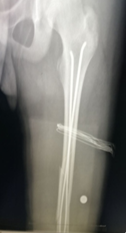

十岁的小星(化名)不小心摔了一跤,当时就感觉到腿部阵阵剧烈的疼痛。父母带着他来到我院骨伤一科就诊,经过相关详细检查后确诊为股骨干骨折,需要动手术治疗。孩子这么小就要开刀动手术?手术会不会有危险?手术后能不能痊愈?这一系列的担心急坏了小星的父母…… 别怕:手术只打一个小孔!“我院最新的弹性髓内钉...